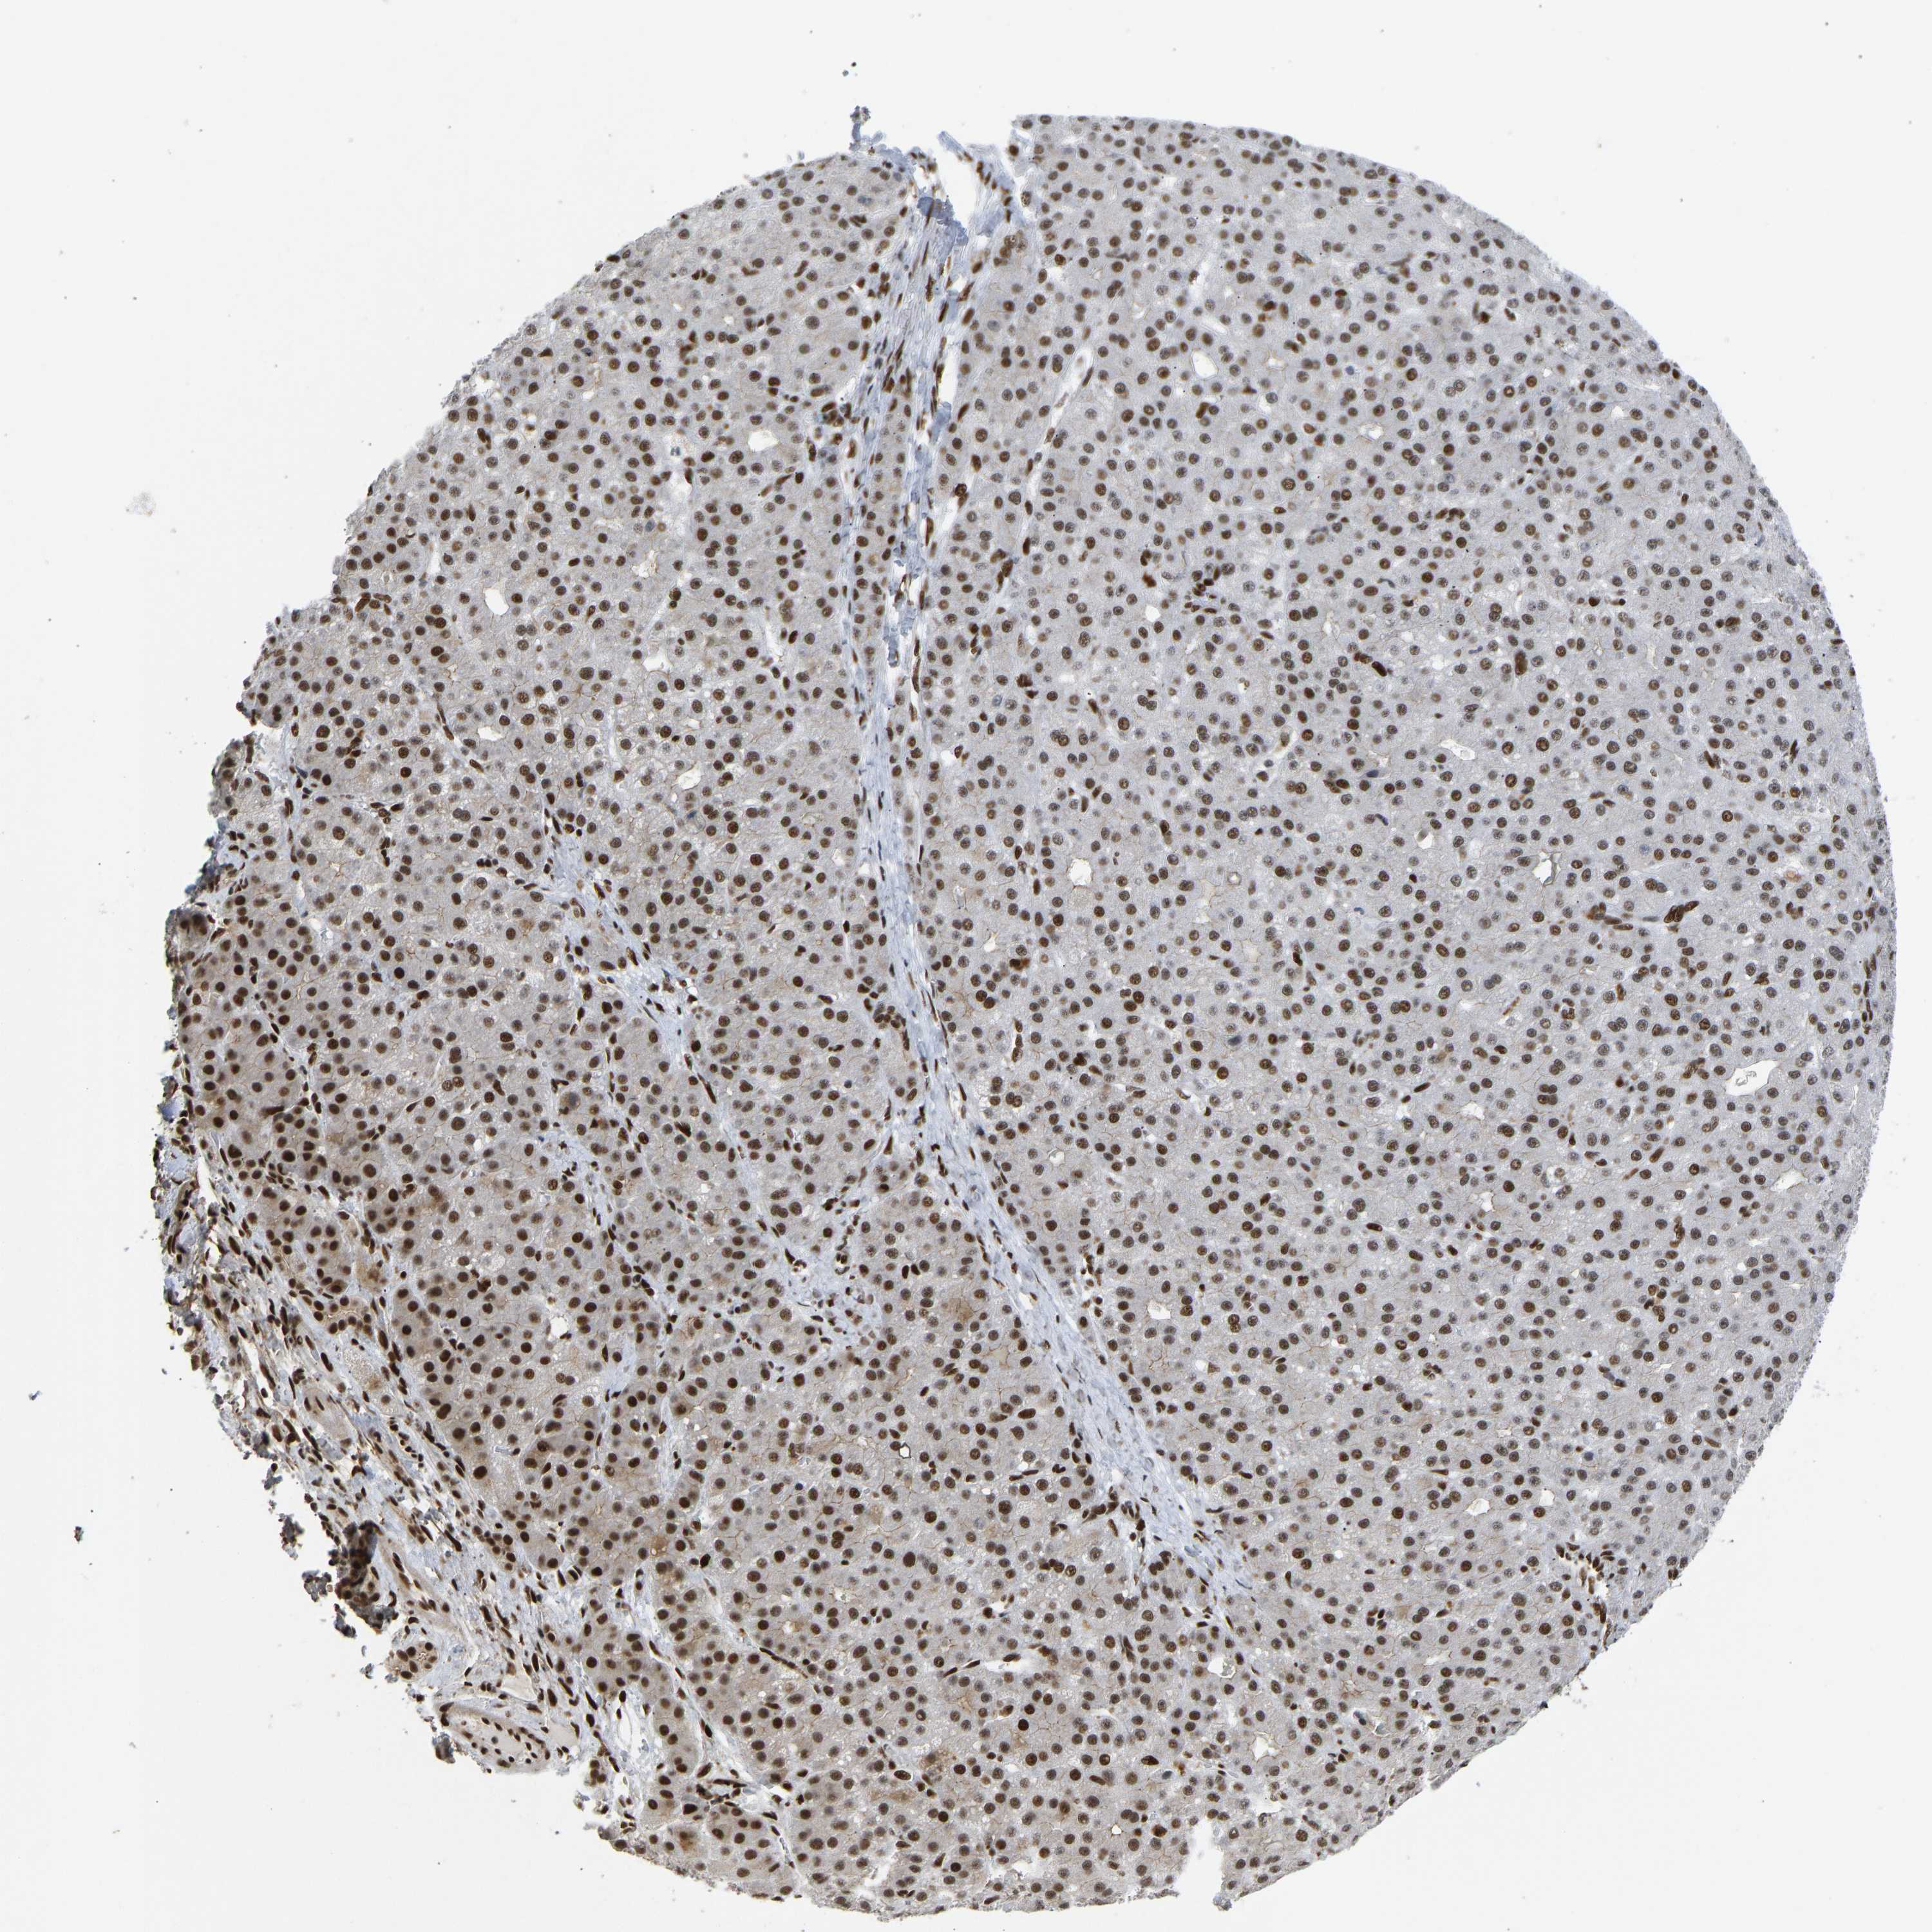

LIVER CANCER - Protein expressioni

A mouse-over function shows sample information and annotation data. Click on an image to view it in a full screen mode. Samples can be filtered based on level of antibody staining by selecting one or several of the following categories: high, medium, low and not detected. The assay and annotation is described here.

Antibody stainingi

Antibody staining in the annotated cell types in the current human tissue is reported as not detected, low, medium, or high, based on conventional immunohistochemistry profiling in selected tissues. This score is based on the combination of the staining intensity and fraction of stained cells.

Each image is clickable and will lead to virtual microscopy that enables deeper exploration of all samples and also displays staining intensity scores, fraction scores and subcellular localization as well as patient and tissue information for each sample.

Antibody HPA017998

Antibody HPA018864

Staining

High

Medium

Low

Not detected

Intensity

Strong

Moderate

Weak

Negative

Quantity

>75%

75%-25%

<25%

None

Location

Nuclear

Cytoplasmic/membranous

Cytoplasmic/membranous,nuclear

Cholangiocarcinoma

Carcinoma, Hepatocellular, NOS